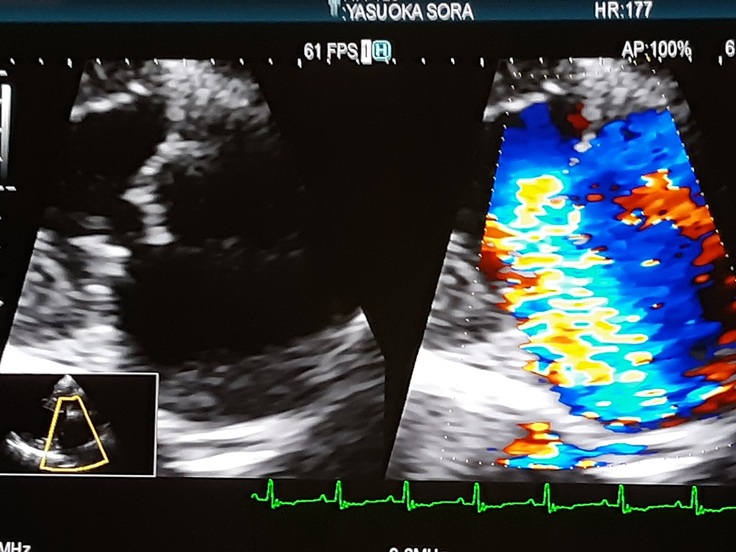

2月10日の心臓検査の診断結果です。

エコー検査結果では左の画像が弁の状態です、弁がぺらぺらに伸びてちぎれていると言われました。右の画像の虹色部分は血液の逆流を示します、ほとんどの血液が逆流しています。

横で寝ているだけでザーザーと心臓から音が聞こえてきます、逆流していると思うだけで怖くて心配で眠れなくなってしまいます。